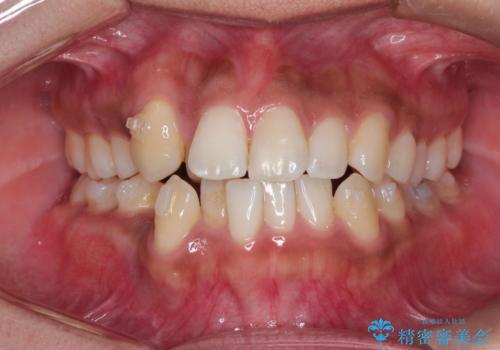

インビザラインと補助装置の併用による八重歯の抜歯矯正

- 八重歯を治したいとのことで来院されました。

重なりが強い右側の上下の歯を1本ずつ抜歯する計画としました。

インビザラインでの治療がご希望でしたが、右上の歯のかさなりが強いところは、補助装置である程度動かしてからインビザラインに移行することにしました。

下顎はインビザラインのみで治療を行いました。